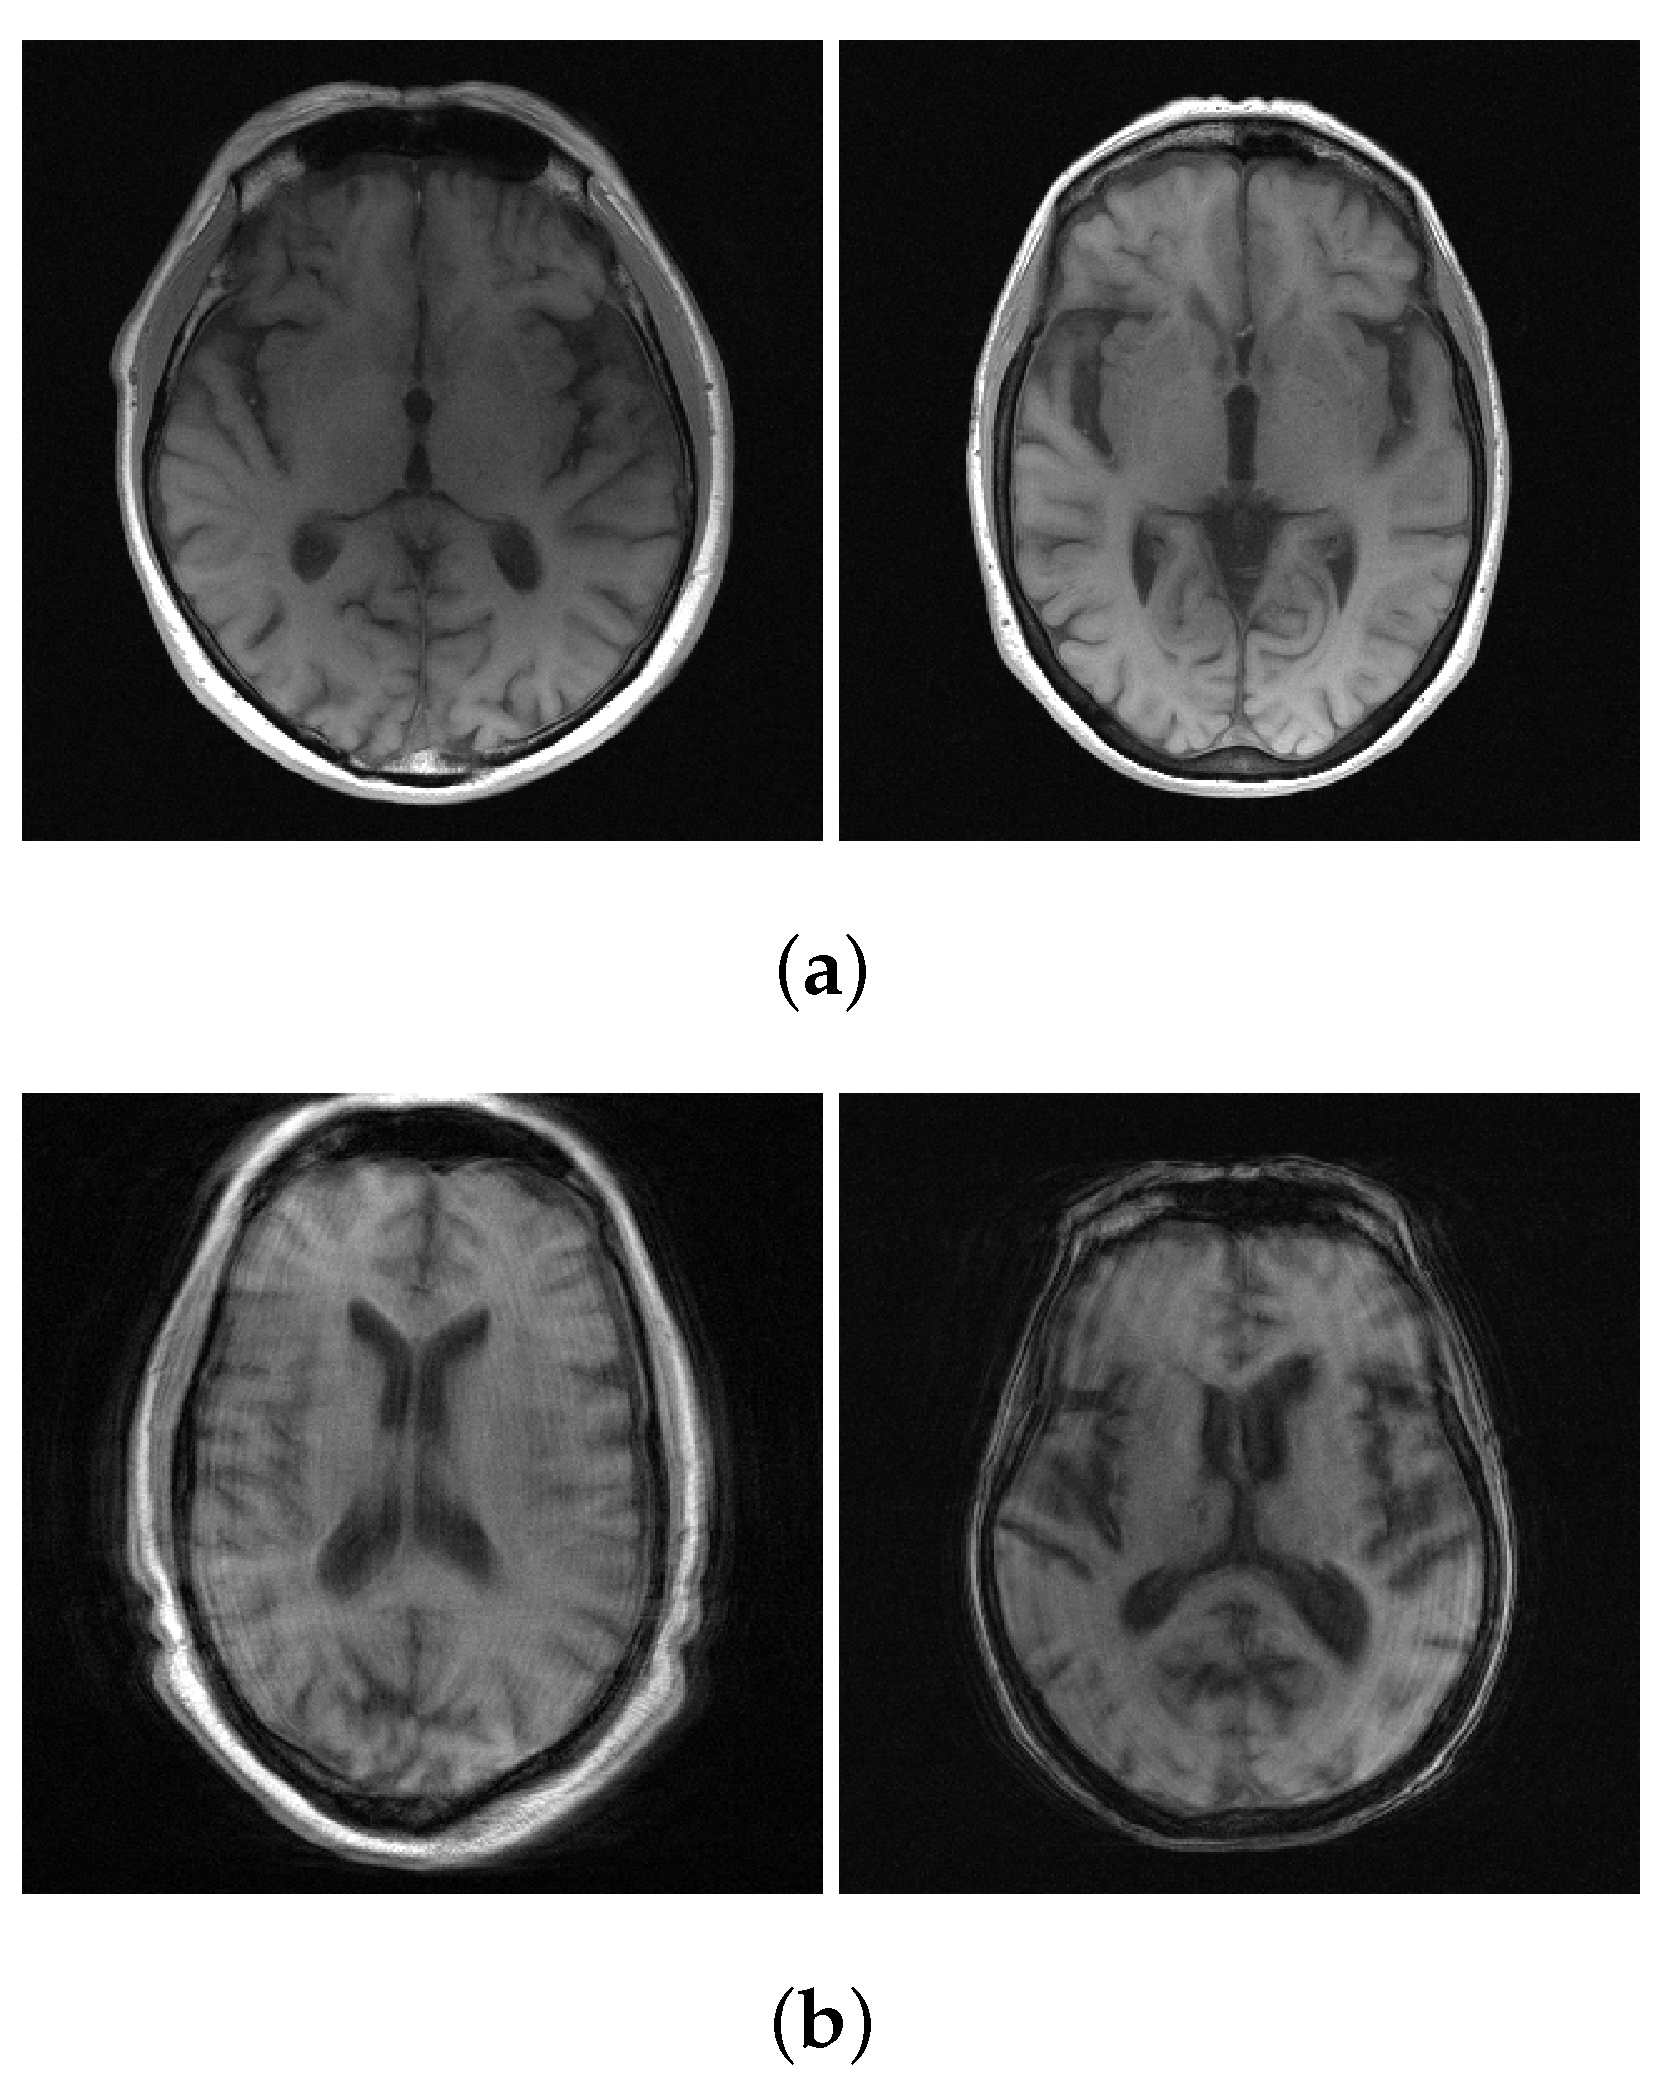

We used T1-weighted MR images of the NYU fastMRI brain dataset [43], which were obtained from four different MR scanners. The number of T1-weighted MR images is 498 scans (axial 7782 slices) for training and 169 scans (axial 2646 slices) for validation. The data used in our study subscribes to the following parameters: magnetic field strength = (1.5, 3) T, the number of multi-receiver coils = (2, 4, 6, 8, 12, 14, 16, 18, 20, 24), matrix size = ((640 × 260), (640 × 272), (640 × 290), (640 × 320), (640 × 332)), resolution = ((0.69 × 0.69), (0.69 × 0.72), (0.72 × 0.72), (0.75 × 0.75)) mm, and slice thickness = (5, 7.5) mm. We used all 7782 slices for training; however, we conducted the validation without using the entire validation dataset, using only 1542 slices and excluding the data with ringing artifacts (as shown in Figure 3).To generate the multi-coil under-sampled k-space to be used for training and validation, multi-coil fully-sampled k-space data was multiplied pixel-wise by a sampling mask. As the sampling mask, equi-spaced sampling masks for regular under-sampling were used, as is shown in Figure 4. The acceleration factor and ACS ratio for sampling are as follows: (2, 10%), (4, 8%), and (8, 4%).

Figure 3.

Examples of the NYU fastMRI brain dataset. (a) Artifact-free T1 weighted MR image; (b) Ringing artifact T1 weighted MR image.